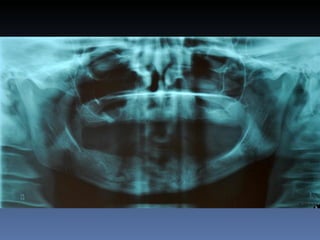

Maria Seemagenn Borges

Diagnóstico: Desdentada

Plano de tratamento: Instalação de 5 implants endo-

ósseos - “Protocolo Branemark”, com carga imediata.